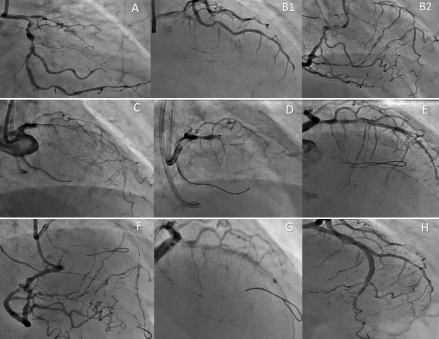

A 60-year-old female with a history of hypertension, diabetes mellitus, and ischemic heart disease presented with severe chest pain that radiated to the neck and was associated with nausea and vomiting. Her EKG showed marked left-axis deviation, ST depressions in V2-V4, and RBBB. She was diagnosed with NSTEMI with a thrombolysis in myocardial infarction (TIMI) score of 5. She was loaded with aspirin and clopidogrel and was taken for left heart catheterization (LHC), which demonstrated three-vessel coronary artery disease with chronic 100% occlusion of the proximal left anterior descending artery, ostial 60-70% stenosis, and proximal 90-95% diseased left circumflex artery, while her right coronary artery had proximal 20-30% obstruction and mid 50-60% with right to left filling. The patient was advised CABG by the heart team, but the patient refused, and PCI was attempted on a shared decision basis. PCI was successful with the use of the Carlino technique: 0.5 ml of contrast dye was injected through a microcatheter to hydraulically recanalise the occlusion. The patient showed dramatic improvement and was discharged home on oral medications.

Treating multi-vessel coronary artery disease and CTO is challenging. PCI, particularly with the Carlino technique, offers a reliable approach. This technique, a modification of contrast-guided STAR, involves gentle contrast injection via microcatheter to modify plaque compliance and provide topographic information with regards to equipment location within vasculature, enhancing procedural success, especially in cases with impenetrable caps or calcified areas.